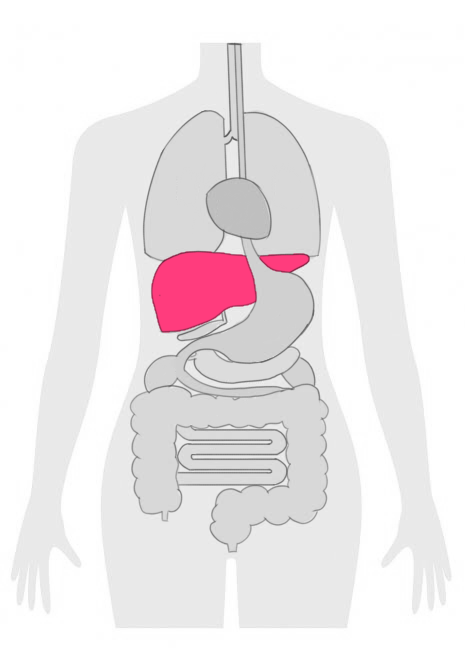

ステージ4の肝臓がんは、がん細胞が肝臓の外に広がり、他の臓器やリンパ節にも転移している状態を指します。

この段階では、がんの大きさや位置に関係なく、がんが体の他の部位に広がっているため、治療のアプローチが難しくなります。

症状としては、黄疸、体重減少、腹部の膨張、疲労感などが現れることが多いです。

ステージ4の肝臓がんは、転移が進行しているため、全身の状態が悪化することも考えられます。